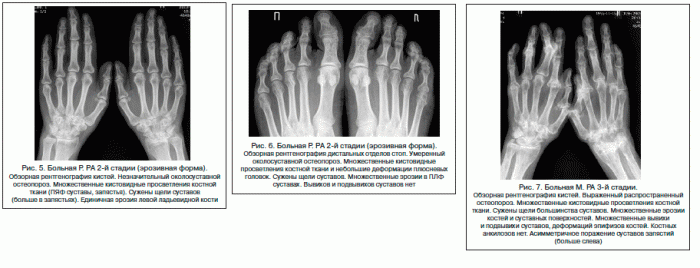

Вторая стадия. Образуются множественные кисты в костной ткани. На рентгеновских снимках отчетливо виден околосуставной остеопороз, межсуставные щели сужаются. Эта стадия может прогрессировать до появления первой эрозии, повреждающей костную ткань. Боль становится более интенсивной и острой, проявляясь не только при движении, но и в покое. В течение дня может ощущаться онемение рук или ног. Припухлость суставов легко прощупывается. На рентгене видны изменения в мягких тканях, окружающих сустав.

Третья стадия. На этой поздней стадии развиваются многочисленные эрозии суставных поверхностей, мышцы, прилегающие к пораженным участкам, атрофируются. На рентгеновских снимках видны признаки остеопороза, множество кист в костной ткани, а также сужение межсуставных щелей, что может сопровождаться вывихами и подвывихами суставов. Кальцификация мягких тканей приводит к образованию ревматоидных узлов диаметром 2-3 см. Боль становится невыносимой даже в лежачем положении, кожа краснеет, а температура тела повышается. В таких случаях пациенту необходимо срочное лечение. На рентгеновских снимках четко видны очаги поражения и деформация суставов.

Третья стадия – умеренный (выраженный) околосуставной остеопороз, множественные кистовидные просветления костной ткани, сужение суставных щелей, множественные эрозии суставных поверхностей (более четырех), множественные выраженные деформации костей, подвывихи и вывихи суставов.